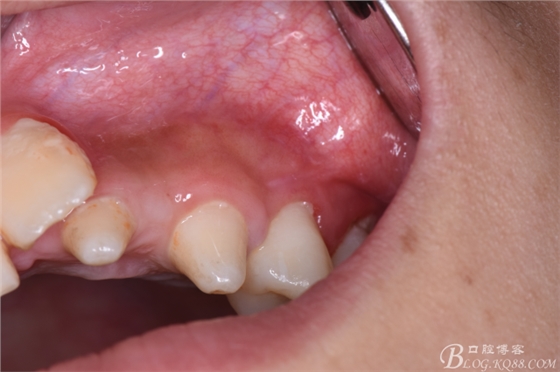

圖5.口內(nèi)觀:22、23區(qū)域的牙齒均為過(guò)小牙、牙冠畸形,24根尖區(qū)未能捫及明顯隆起,但cbct的精準(zhǔn)定位,確定切口應(yīng)做在24根尖區(qū)的前庭溝內(nèi)。

圖6.患者的口腔衛(wèi)生不佳,建議潔牙。